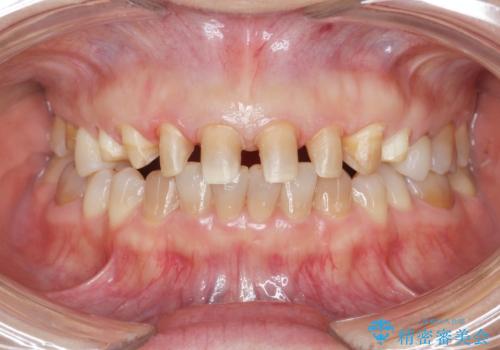

- 十数年前に行った、前歯のラミネートベニアの継ぎ目が見えるようになってきて見た目が気になる。

この際もう一度ラミネートでやり替えるのではなく、強度にも優れるクラウンにしたいと希望され来院されました。

ラミネートを丁寧に除去したのち、ジルコニアクラウンを作製し審美性の回復・向上を計画します。